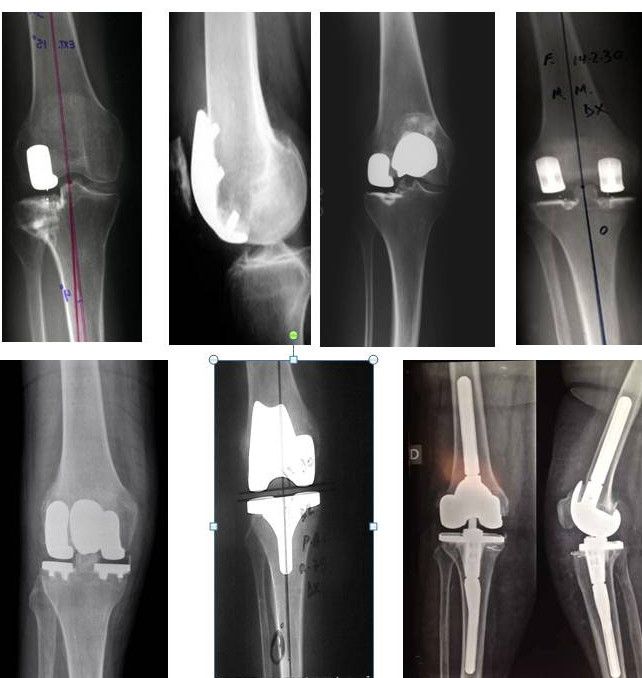

Protesi monocompartmentali : compartimento femoro tibiale mediale e laterale : Questo tipo di protesi è utilizzato per il trattamento di forme non gravi di gonartrosi. Nei centri con le maggiori casistiche del settore rappresentano mediamente il 20 per cento del numero totale di protesi di ginocchio eseguite. La protesi monocompartimentale è indicata nei pazienti con gonartrosi che interessa un solo compartimento del ginocchio, o affetti da necrosi isolata di un condilo femorale oppure di un emipiatto tibiale. Il paziente candidato è tra i 55 e i 60 anni, non in soprappeso; la motilità del ginocchio non dovrebbe essere del tutto compromessa ( almeno 90° di flessione ed un deficit di estensione non superiore al 10% ); non devono essere presenti deformità angolari importanti del ginocchio ( non superare i 15° di deformità in varismo o in valgismo ) ; il legamento crociato anteriore deve risultare ancora efficiente. La tecnica consiste nell’applicazione della protesi monocompartimentale attraverso una mini incisione della cute di circa 8-10 cm. Ed attraverso una mini-incisione della capsula articolare. L’aggressione chirurgica è molto limitata, non prevede il sacrificio di nessuna struttura legamentosa, la rotula non viene lussata durante la procedura ed il tendine quadricipitale non risulta del tutto interessato dalla incisione chirurgica. La fisioterapia viene iniziata 2 –3 ore dopo l’intervento con la possibilità di mobilizzare immediatamente e completamente il ginocchio e di alzarsi dal letto con il carico completo sull’arto operato, sempre dopo poche ore. Questo tipo di intervento chirurgico non richiede ricoveri prolungati. Sono sufficienti 7- 10 giorni,  e sono descritti esperienze anche solo con ricoveri che prevedono soltanto una notte di degenza. Alla dimissione al paziente viene consigliata una profilassi anti-tromboembolica che viene proseguita a domicilio per 6 settimane così come pure la fisioterapia, proseguita a domicilio o presso un centro riabilitativo.  Il paziente utilizza un appoggio ( stampella canadese ) durante il cammino per 4 settimane e l’articolarità normale del ginocchio operato è recuperata in circa 2 –3 settimane. La tumefazione articolare si risolve in genere in 6 – 8 settimane ed il paziente recupera l’efficienza completa chirurgica due mesi dopo il trattamento chirurgico. Dopo questo periodo è prevista la possibilità di utilizzare la bicicletta e di effettuare attività sportive in progressione come palestra, golf, tennis e anche sci.

Protesi monocompartmentali : compartimento femoro-rotuleo: Questo tipo di protesi è indicata per artrosi limitata al comportamento femoro rotuleo quindi  in casi altamente selezionati: Artrosi Rotulea e della Troclea Femorale “Isolate” o nella associazione di entrambe e quindi con le restanti parti articolari del ginocchio non danneggiate. Ovviamente ciò restringe l’età dei candidati ideali a pazienti relativamente giovani in quanto pazienti anziani difficilmente presentano solo un’artrosi isolata della femoro-rotulea. Anche in questo caso sono richieste nel candidato ideale una buona articolarità del ginocchio, non una eccessiva deviazione assiale e una buona stabilità articolare. L’approccio chirurgico è sovrapponibile a quello della protesi monocompartimentale femoro-tibiale, con una incisione cutanea più centrata sulla rotula ed una artrotomia pararotulea mediale. In questo tipo di impianto la rotula viene “lussata” onde consentire una buona visione della sua superficie articolare e per capire se oltre alla protesizzazione della gola femorale sia necessario anche protesizzare la rotula od, in caso di danno cartilagineo minimo, sia possibile limitarsi semplicemente a gesti accessori quale la denervazione della rotula. Il decorso post-operatorio è del tutto sovrapponibile a quello della  protesi monocompartimentale femoro-tibiale con un recupero della funzionalità articolare molto più simile al ginocchio normale rispetto ad un impianto più invasivo come una protesi totale. Anche in questo caso, nel postoperatorio, è necessario l’utilizzo di stampelle per circa un mese senza particolari limitazioni al carico e la necessità di fisioterapia prima della ripresa graduale sportiva.

Protesi bimonocompartmentali : compartimento femoro tibiale mediale+ laterale: Anche se la bimono prevede l’utilizzo in associazione di 2 protesi mono compartimentali essa rappresenta sempre, da un punto di vista strettamente chirurgico, un presidio notevolmente, meno invasivo della protesizzazione totale. Infatti, l’apparato legamentoso non viene lesionato, non necessita di uno strumentario intramidollare, pur consentendo una correzione tridimensionale della deformità artrosica. In caso di fallimento, il ricorso alla protesizzazione totale, in virtù della scarsa resezione ossea, che ne preserva il bone stock, non presenta eccessivi problemi e l’infezione, qualora si presenti, dovrebbe risultare più facilmente risolvibile. Accanto a questo ne esistono di pratici anche per il paziente quali: ridotte perdite ematiche, minor rischio di trombosi venosa e soprattutto la possibilità di mantenere una propricettività e biomeccanica articolare simile al ginocchio normale grazie al mantenimento dell’apparato legamentoso incluso il legamento crociato anteriore. Chiaramente non sono pazienti ideali per questo tipo di impianto pazienti con lassità dei crociati ed artrosi associata della femoro-rotulea estendendo le indicazioni della protesi monocompartimentale femoro-tibiale alla presenza di un’artrosi estesa ad entrambi i compartimenti mediale e laterale.  L’intervento chirurgico è sovrapponibile a quello di una protesi totale ma con il vantaggio di non usare strumentari diallineamento intramidollari. Il decorso post-operatorio è leggermente più rallentato rispetto ad una di una protesi monocompartimentale ma con un recupero articolare senz’altro maggiore rispetto una totale.

Protesi bimonocompartmentali : compartimento femoro tibiale + femoro-rotuleo: In alcuni casi in cui oltre ad un danno di un comparto femoro-tibiale  sia associato un danno al comparto femoro-rotuleo è possibile associare due protesi monocompartimentali per entrambi i compartimenti. Mantenendo gli stessi requisiti delle protesi monocompartimentali isolate come la presenza di una buona stabilità legamentosa, la presenza di una buona articolarità e l’assenza di significative deviazioni assiali nella associazione delle 2 protesi è fondamentale una ottima pianificazione della taglia femorale,  considerando che i due scudi femorali non devono arrivare a sovrapporsi pena il  fallimento dell’impianto. Questi tipo di associazione ha avuto un ampio riscontro, da pochi anni,  anche tra le aziende produttrici di protesi che, intuendone le potenzialità,  sono arrivate loro stesse a proporre sul mercato impianti che prevedono scudi femorali che in unico pezzo inglobano sia condilo femorale sia troclea femorale.  Il decorso post-operatorio è del tutto sovrapponibile a quello di una protesi totale, in quanto in quasi la totalità delle protesi femoro-rotulee  è necessario l’utilizzo di un sistema endomidollare di allineamente. I vantaggi biomeccanici sono sovrapponibili a tutti gli impianti fino ad’ora illustrati.

Protesi totali: La protesi totale di ginocchio eseguita con la tecnica convenzionale risulta ancora oggi in molti centri ortopedici il trattamento standard nelle forme di gonartrosi più o meno diffuse  non sensibili alla terapia non chirurgica. Essa prevede la protesizzazione sia di entrambi i condili femorale ed emipiatti  tibiali utilizzando spesso strumentari endomidollari nel controllo dell’ allineamento dell’impianto.  Esistono differenti tipi di protesi totale di ginocchio, una prima differenza è costituita dalla presenza od assenza del legamento crociato posteriore, un’ ulteriore differenza è costituita dalla tipologia del piatto tibiale che può essere più o meno congruente o più o meno mobile nei vari piani. Tendenzialmente gran parte dei chirurghi preferisce l’utilizzo di cemento, spesso impregnato da antibiotico, per la fissazione della protesi all’osso, anche se recentemente sono disponibili protesi che grazie a rivestimenti particolari consento una rapida osteointegrazione dell’impianto nell’osso. Altro punto di discussione è la protesizzazione della rotulain associazione a quella del femore e della tibia, in quanto a tutt’oggi è ancora controversa, in quanto non vi e’ un accordo in letteratura sulla sua efficacia o necessità. Convenzionalmente  la tecnica tradizionale di protesizzazione con protesiti totale convenzionale prevede un’ampia dissezione dei tessuti articolari del ginocchio per ottenere un’ adeguata esposizione dei tessuti scheletrici femorali e tibiali sacrificando entrambi i legamenti crociati. L’incisione chirurgica è longitudinale di circa 20 cm, centrata sulla rotula che viene quindi lussata lateralmente. Esistono però metodiche più recenti che prevedono incisioni molto più ridotte e che, con l’aiuto di appositi strumentari, permettono l’impianto di protesi tradizionali con una tecnica mini-invasiva anche senza la lussazione della rotula ma che impongono ovviamente una ottima padronanza chirurgica. Il candidato ideale  per una protesi totale di ginocchio è rappresentato da un paziente anziano con quadro di gonartrosi avanzata che interessa più compartimenti del ginocchio con associato spesso significative lassità legamentose o riduzioni dell’articolarità del ginocchio.